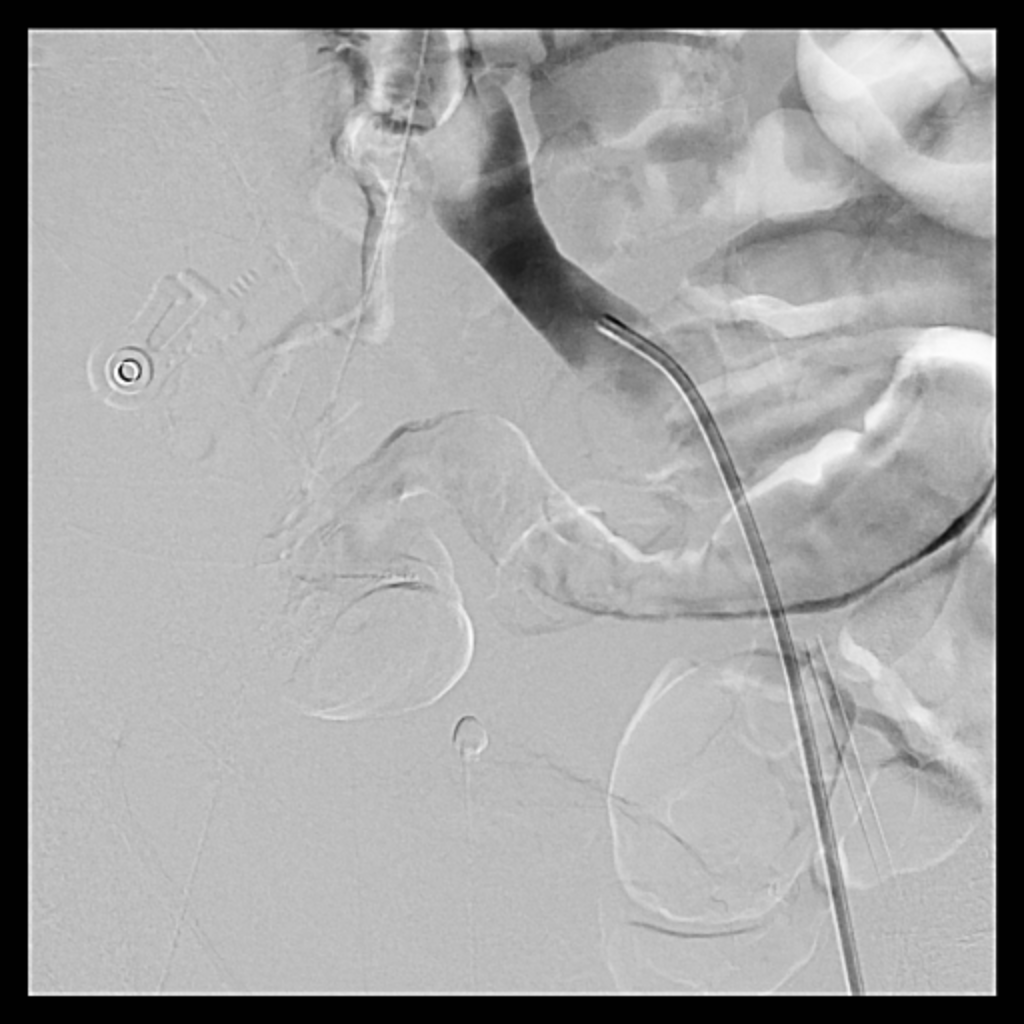

Venous access was obtained and venography confirmed heavy thrombus burden; therefore, the initial 6 Fr sheath was upsized to a 9 Fr sheath. Two Terumo stiff wires were advanced into the IVC to secure stable access. Mechanical thrombectomy using the Boston Scientific AngioJet system was performed from the right iliac vein to the right common femoral vein. During venography, unexpected early arterial opacification suggested an iatrogenic artery-to-vein fistula. Iliac angiography was then performed, revealing a total occlusion of the right common iliac artery with collateral reconstitution. To restore arterial flow and seal the fistula, a contralateral approach was used. A wire successfully crossed the occluded segment into the true lumen, followed by deployment of a covered stent. Final angiography showed complete closure of the fistula and restored antegrade arterial flow without distal embolization. The patient remained hemodynamically stable.